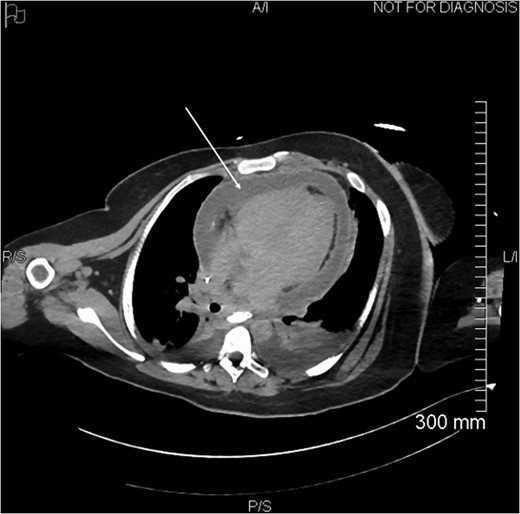

Proximal end of the double pigtail drain externalizes in the pericardium (arrow).